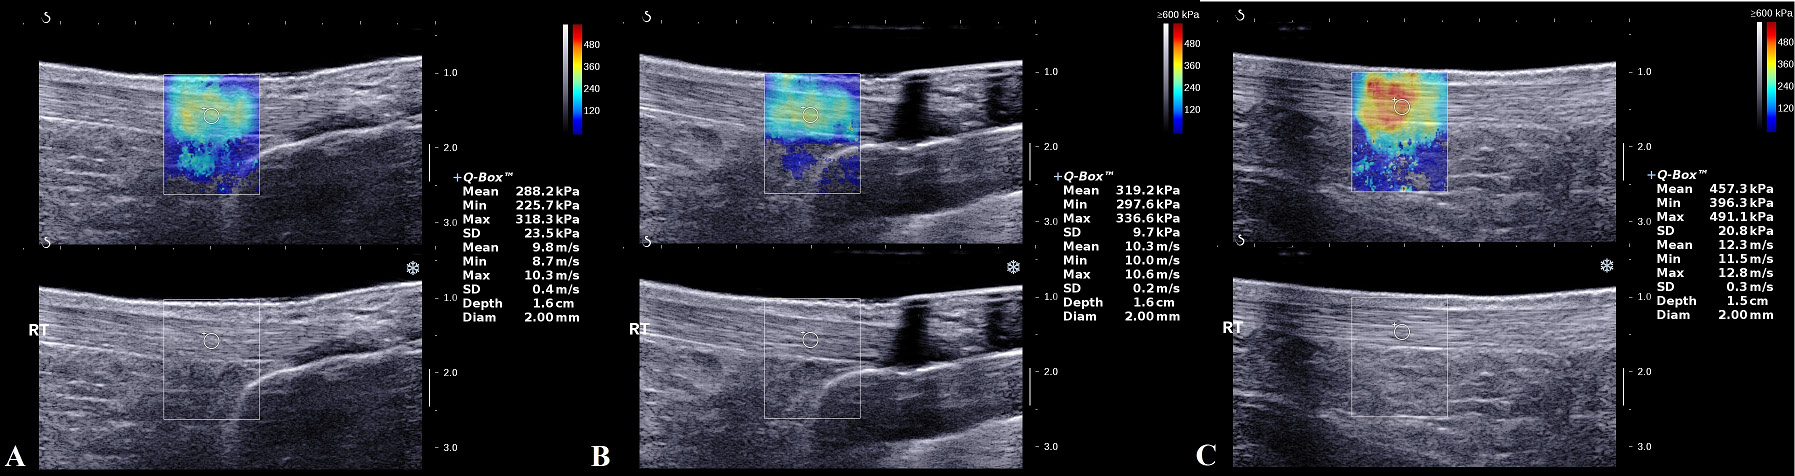

Shear wave ultrasound elastography was performed for the upper left Achilles tendon, middle left Achilles tendon, lower left Achilles tendon, upper right Achilles tendon, middle right Achilles tendon, and lower right Achilles tendon. It was performed for the most suspicious area detected with the B-mode grayscale sonography. The results were analyzed based on color images (semi-quantitatively) and by rigidity of tissue in the region of interest (ROI; quantitatively). The meaning of the colors is: blue – low rigidity, turquoise – intermediate rigidity, yellow to red – high rigidity. The Young’s modulus was used for a quantitative assessment of shear wave ultrasound elastography. The maximum speed of the shear wave was 500 kPa/13 m/s with 2 cm depth. In the ROI, mean and maximum rigidity and shear wave speed were evaluated. A total of 2 mm was the standard diameter of the ROI.3 The representative images for B-mode grayscale sonography and shear wave ultrasound elastography are presented in Figure 2. The characteristics of the most auspicious area in the B-mode grayscale sonography were: the irregular thickening around the Achilles tendon, heterogeneity of echotexture of the tendon and calcification of the calcaneal attachment. Shear wave elasticity less than 350 kpa (10 m/s) was considered tendinopathy.

Shear wave ultrasound elastography

Asymptomatic tendons were visible as red (high rigidity) and symptomatic tendons as blue (low rigidity) or turquoise (intermediate rigidity) images. Tendon rigidity of symptomatic tendons were lower than that of asymptomatic tendons. Shear wave ultrasound elastography results for Achilles tendons was reported in Table 2. According to these measurements, 39 (46%) out of 84 tendons had tendinopathies. Among them, 29 (34%) were asymptomatic and 10 (12%) were symptomatic. The elasticity values of the symptomatic tendons were lower than those of the asymptomatic ones (p = 0.044, Mann–Whitney test).